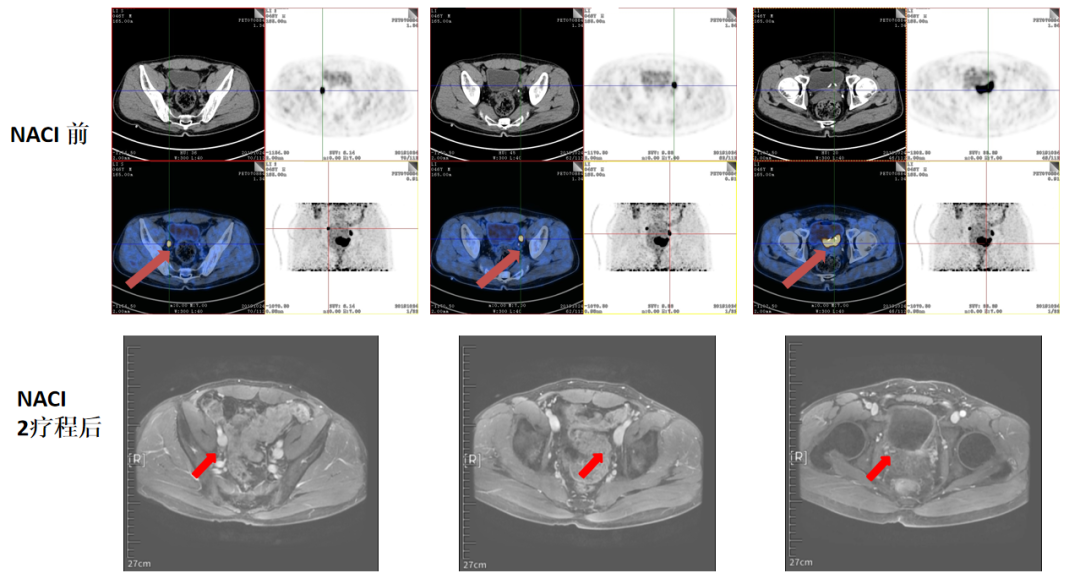

PET-CT延迟成像(2019-10,图1):膀胱左侧壁及后壁增厚,累及双侧输尿管开口,局部与左侧精囊腺分界不清,利尿延迟显像FDG代谢异常增高SUVmax=32.3。双侧髂外血管旁见多枚淋巴结影,较大者约15*10mm位于左侧,利尿延迟显像FDG代谢增高,SUVmax=25.2-28.5。

图1.PET-CT延迟成像(2019-10)

2个疗程NACI后影像学评估达到iPR(图3)。

图3. NACI 2疗程后影像学评估